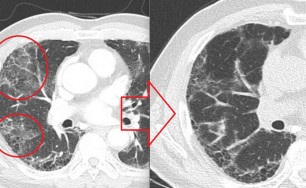

이런 형태의 기침은 엑스레이상 정상인 경우가 대부분입니다.

원인은 기도의 광범위한 상피세포의 손상과 탈락입니다.

기도의 상피세포가 손상을 받으면 점액 섬모의 청소장애가 나타나 기침을 유발합니다.